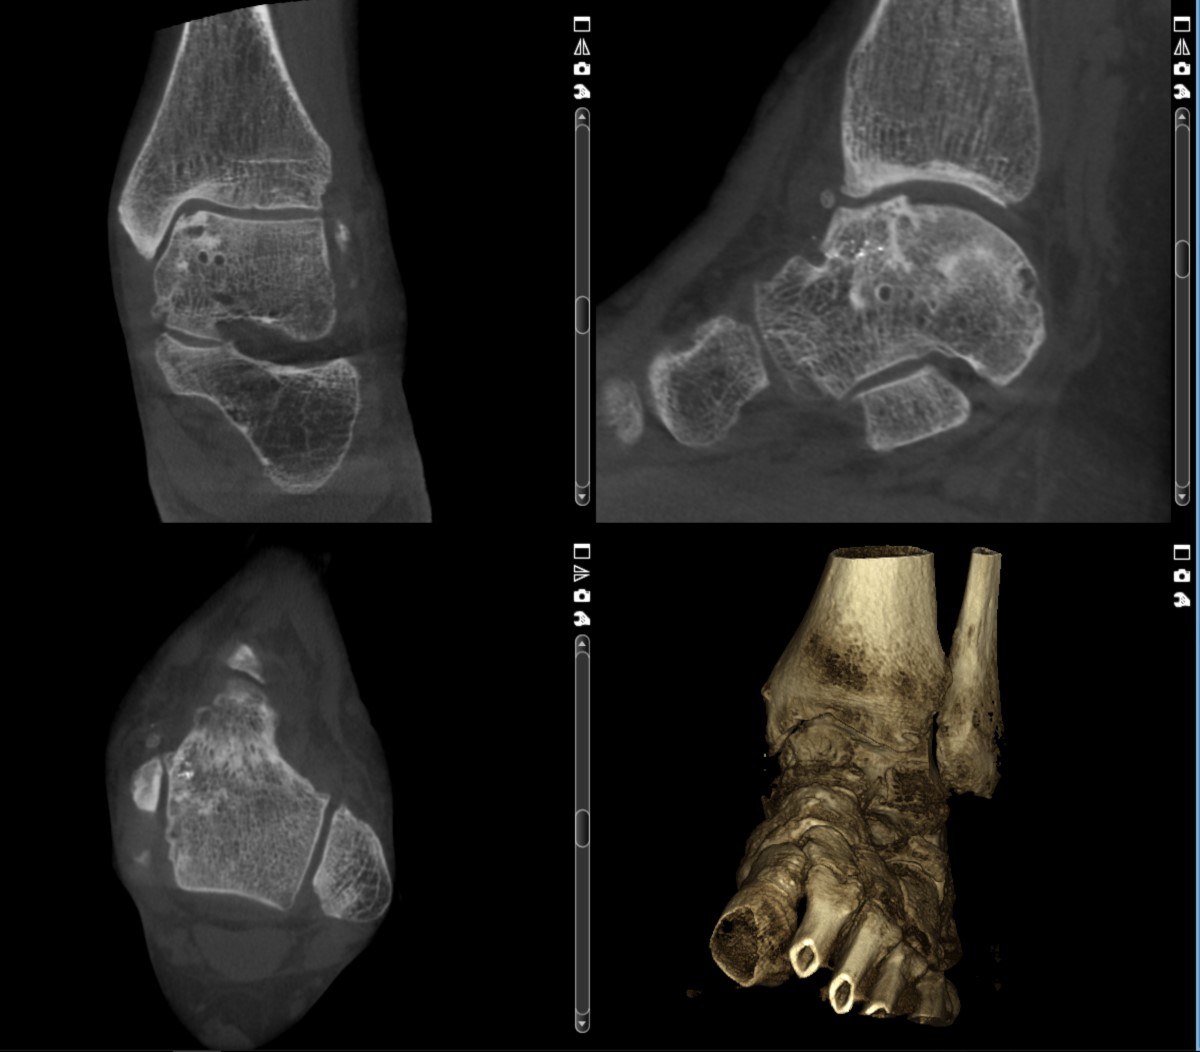

DVT oberes Sprunggelenk:

40 Jahre alte Patientin mit zunehmenden Schmerzen am oberen Sprunggelenk. Sprunggelenkbruch vor 20 Jahren. Die DVT zeigt kleinste Zysten im Sprungbein. Knöcherne Ausziehungen (Osteophyten) am vorderen Gelenkspalt können exakt lokalisiert werden.